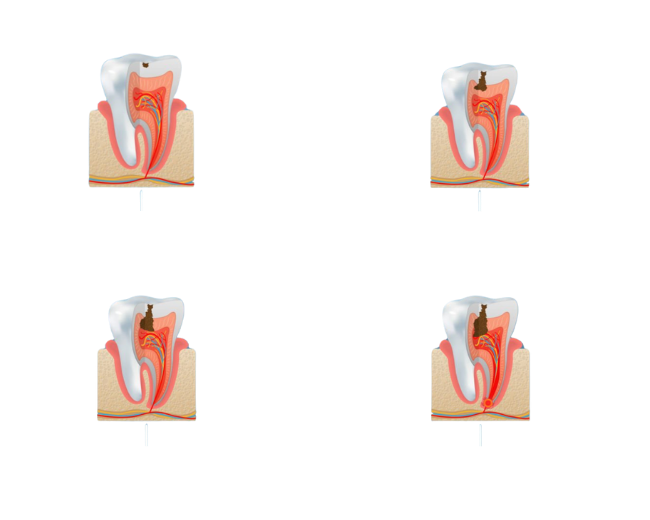

Traitement Canalaire

Sauver une Dent Infectée en Profondeur.

Le traitement endodontique, couramment appelé traitement de racine, consiste à nettoyer et désinfecter l’intérieur de la dent lorsqu’une carie profonde ou une infection atteint la pulpe dentaire. Cette intervention permet de conserver la dent en éliminant la douleur et l’infection, tout en évitant son extraction. Une fois les canaux nettoyés et obturés, la dent est restaurée, souvent à l’aide d’une couronne, pour retrouver toute sa solidité et sa fonction.